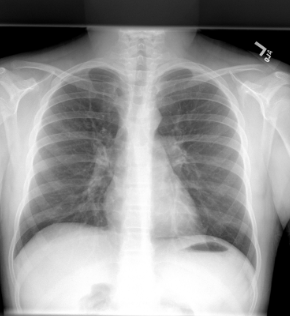

Nadia, short for Not A Doctor but an Inference Assistant, is a web-based AI diagnostic tool that takes in wavelength recordings of users breathing from a stethoscope and coughing and outputs what disease a user most likely has with a confidence score. It also outputs sample X-rays of lungs that have the disease and labels of what differentiates that from a normal set of lungs.

We first normalized and standardized data from Kaggle using pandas that had wavelength recordings of stethoscope data and coughs. Then, we applied audio augmentation techniques like adding Gaussian white noise, time stretch, pitch shift, and time shift so that we could get 6000+ samples to train a neural network on. Then, we applied a Fourier transform to all those samples to get 6000+ spectrograms that had the metadata (age, gender, ID). Then, we trained an EfficientNet CNN model on that data. We also trained another neural network on the metadata on age and gender and combined the results to get a cohesive conclusion. We fetched the result from the model and used a hash map to match the disease to a labelled X-ray about what in the lungs indicate the disease. To create the labeled X-ray, we passed in a PNG file of a sample X-ray to Gemini and type of disease and it returned where and what about the X-ray signaled a disease. Then, we used Figma Make to create the actual labelled X-ray, using the coordinates Gemini gave to create a coherent label for each disease in the model. We used React for the frontend and FastAPI for the backend.